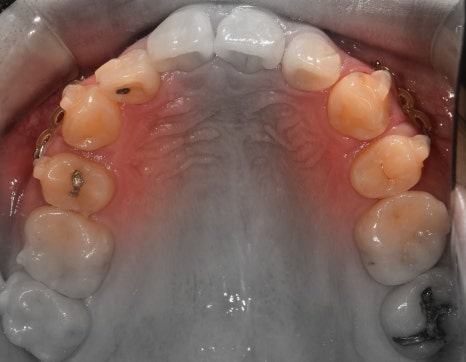

앞서, 1치대 1치 관계에 있던 교합관계들이

1치대 2치의 관계로 바뀐것을 볼 수 있으면서

길쭉하게 느껴졌던, U shape 형태의 악궁이

딱 보기 좋은, U shape 로 바뀌었죠.